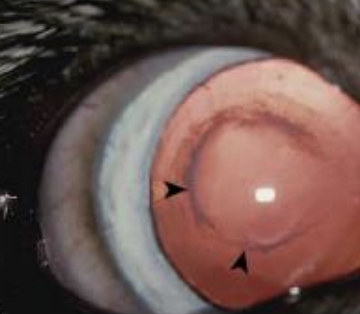

Tapetum lucidum

What structure/layer, found in the dorsal choroid, is shown in the image and is not seen in pigs?

<p>What structure/layer, found in the dorsal choroid, is shown in the image and is not seen in pigs?</p>